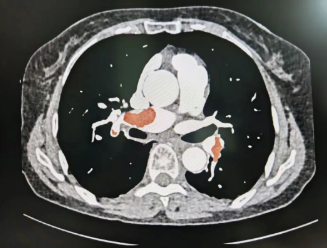

这是一场惊心动魄的生命接力,也是一次多学科协作创造的医疗奇迹。日前,一名74岁女性患者因“反复头晕伴劳累3天,加重伴晕厥1次”被送至我院急诊。经检查提示其左右肺动脉主干及多级分支广泛栓塞,右肺动脉近乎完全闭塞,左肺动脉主干堵塞高达85%,同时并发下腔静脉及肝静脉栓塞、双下肢血管完全闭塞,生命危在旦夕。

患者出现进行性呼吸困难与频繁晕厥,被确诊为梗阻性休克。常规手术或溶栓操作可能引发致命性血栓脱落,救治难度极大。我院迅速启动多学科会诊(MDT),重症医学科、普外科、超声科、放射科专家共同研判,制定急诊肺动脉取栓术方案。